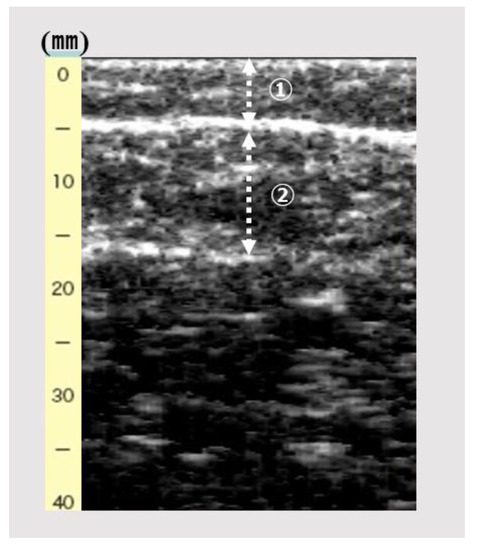

| Ultrasonography | ||||

| SFT; mm | 4.1 ± 2.2 | 2.6 ± 1.5 | 5.0 ± 2.1 | <0.001 |

| GT; mm | 13.0 ± 2.2 | 13.6 ± 2.6 | 12.7 ± 1.8 | <0.01 |